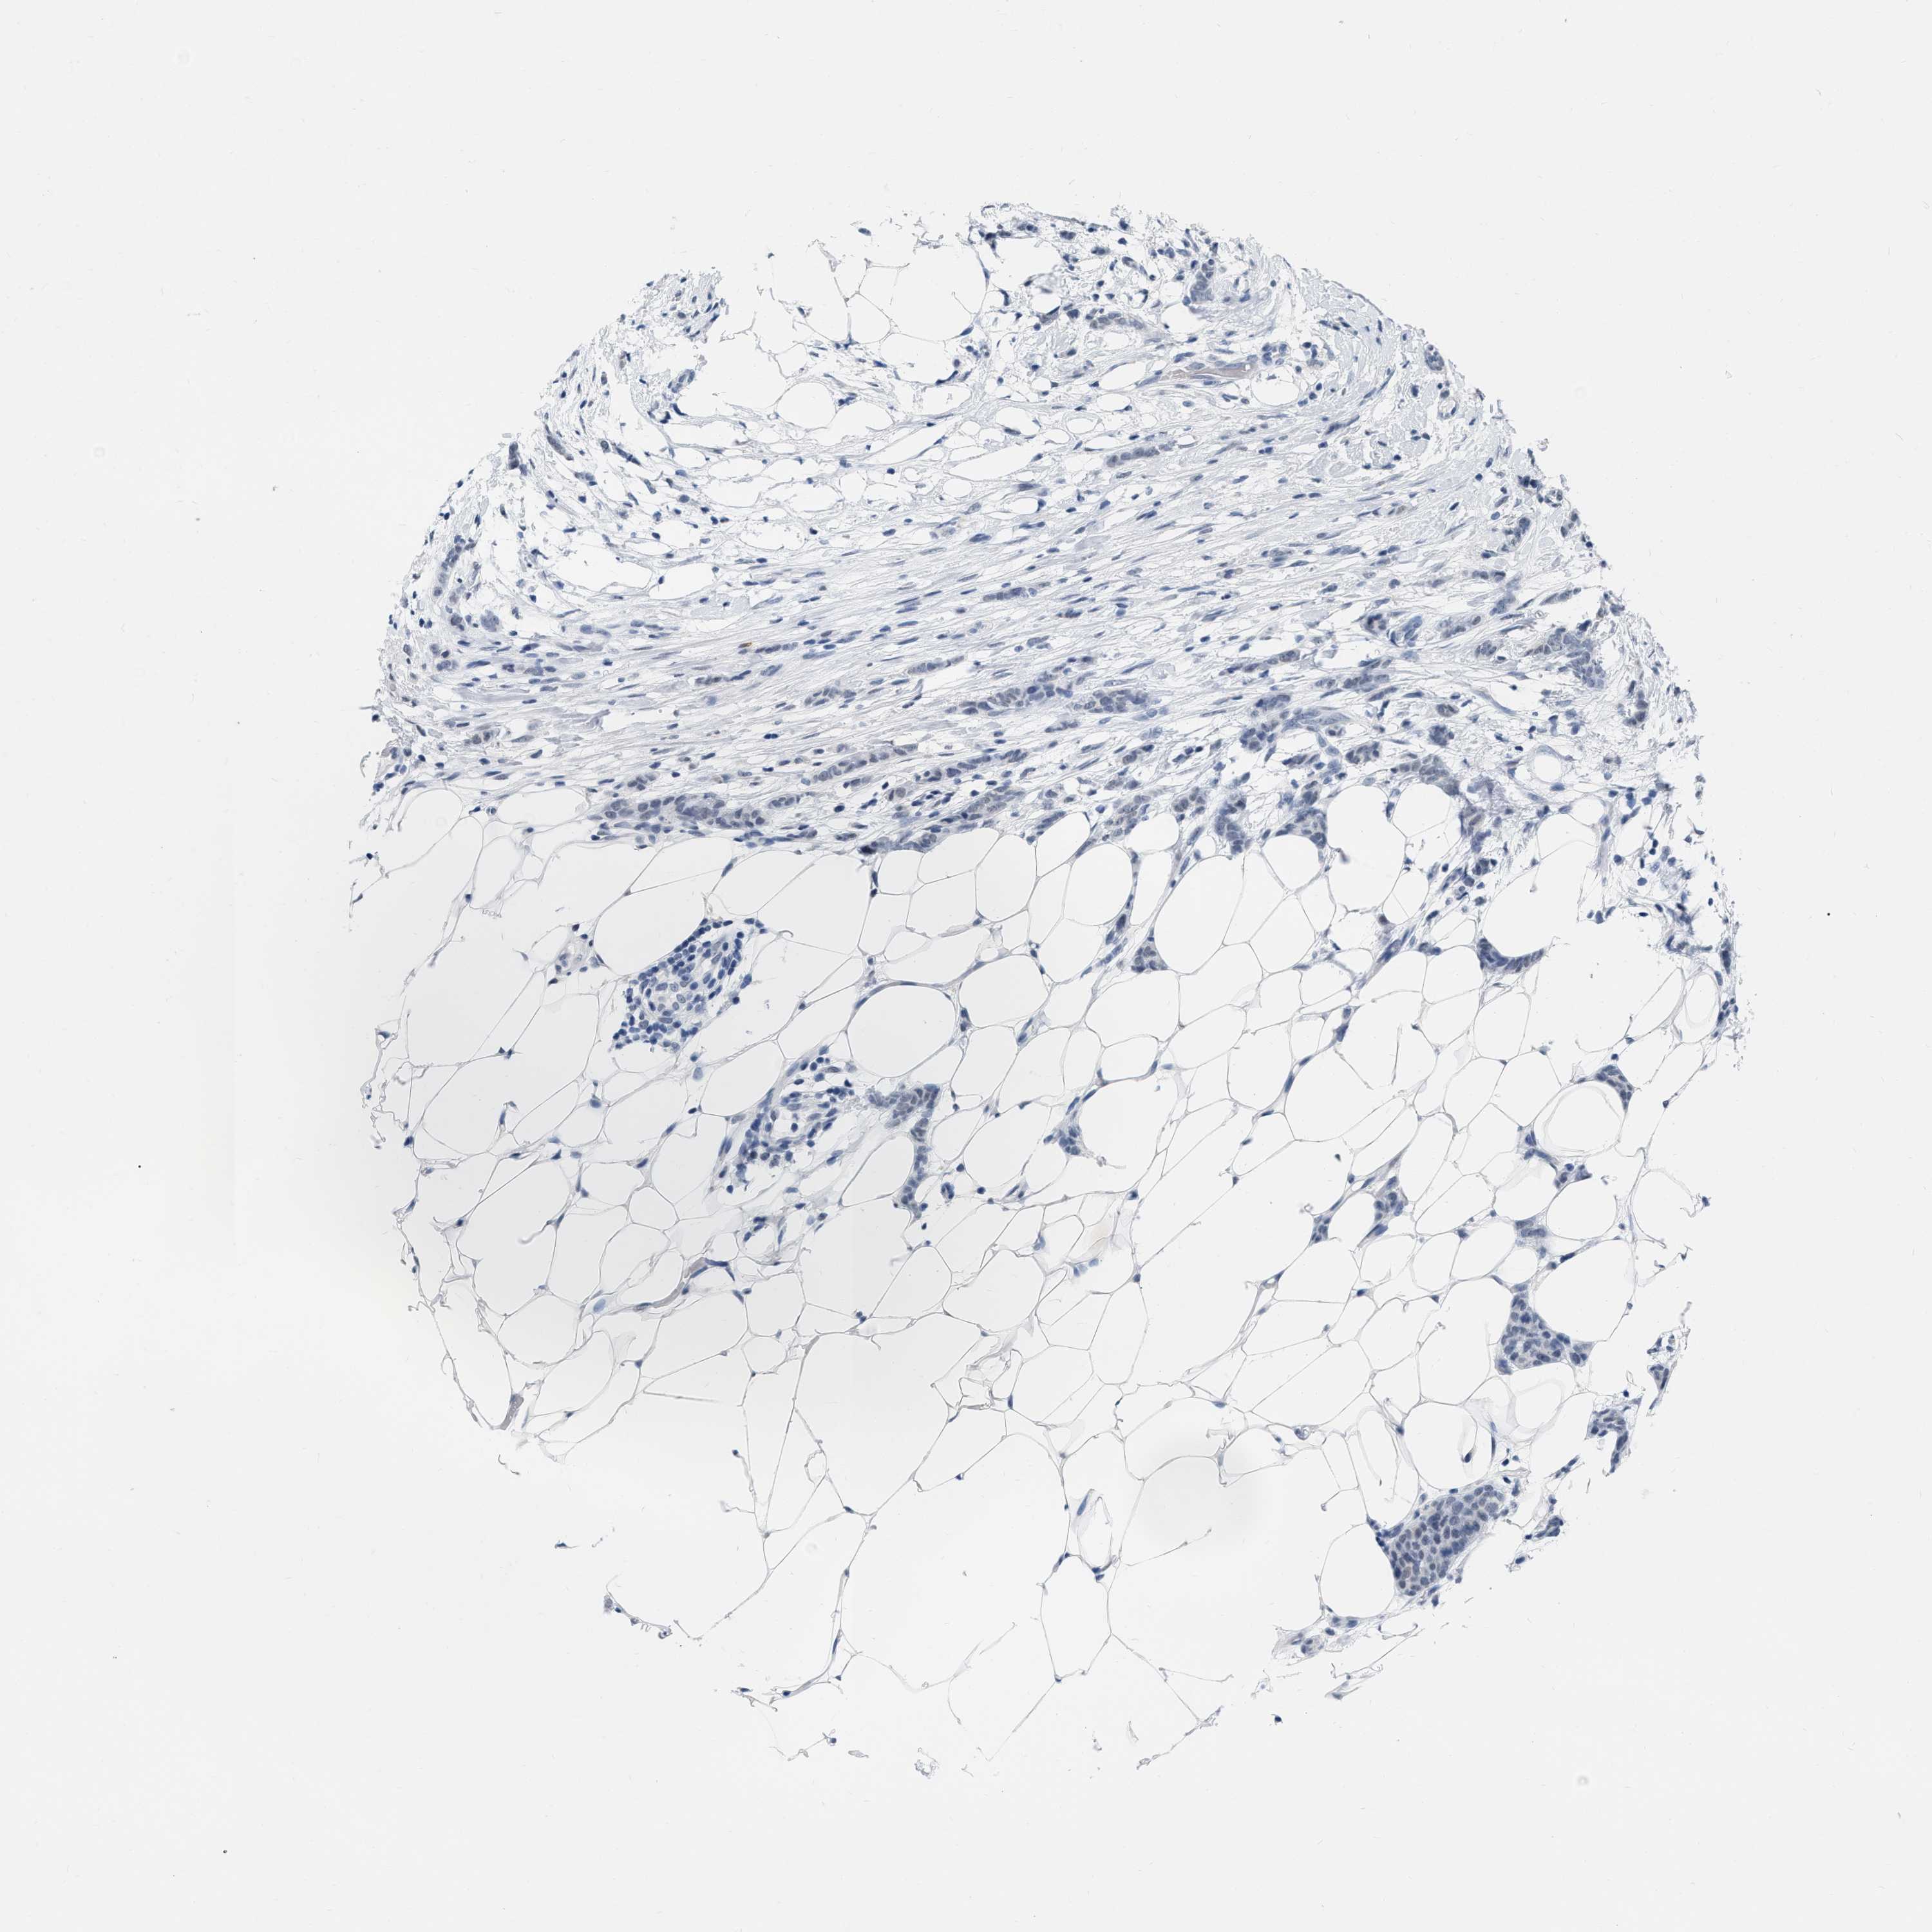

CANCER BREAST CANCER Show tissue menu

BRCA TCGA BRCA VALIDATION PROTEIN EXPRESSION

ANTIBODIES

AND

VALIDATION